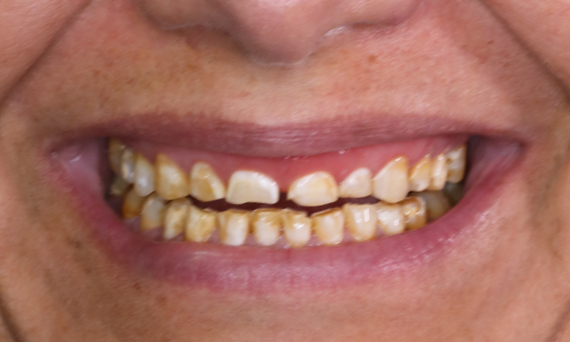

Quadrant rehabilitation in 2 sessions

Ten VITA Suprinity PC single crowns

The patient wanted a beautiful smile. As teeth 15 to 25 are all visible, the decision was made to use a highly esthetic ceramic for all 10 of them. Due to the extensive consultation and the implementation with a mock-up, the restoration was carried out in two sessions with CEREC.

Before: Patient, dissatisfied with her smile due to tooth discoloration.

After: Ten highly esthetic single crowns, individualized with stains.